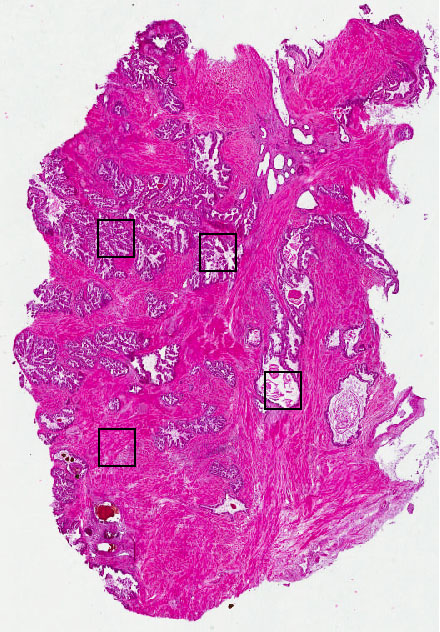

Cell types%

Glandular cells:

30

Smooth muscle cells:

65

Other cell types:

5